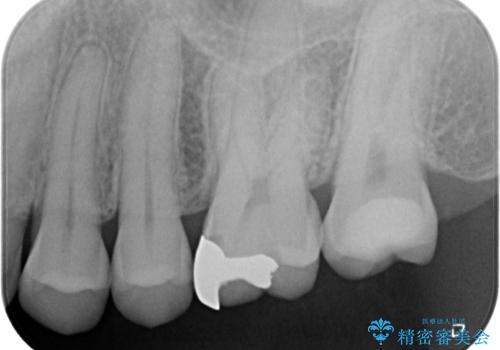

- 数年前他院にて治療した銀歯をやり替え希望の患者様です。

拡大鏡下で、銀歯、むし歯の除去を行い、セラミックインレーに適した形に整えました。

精度の良いインレーを製作するために、シリコーンにて型どりしました。